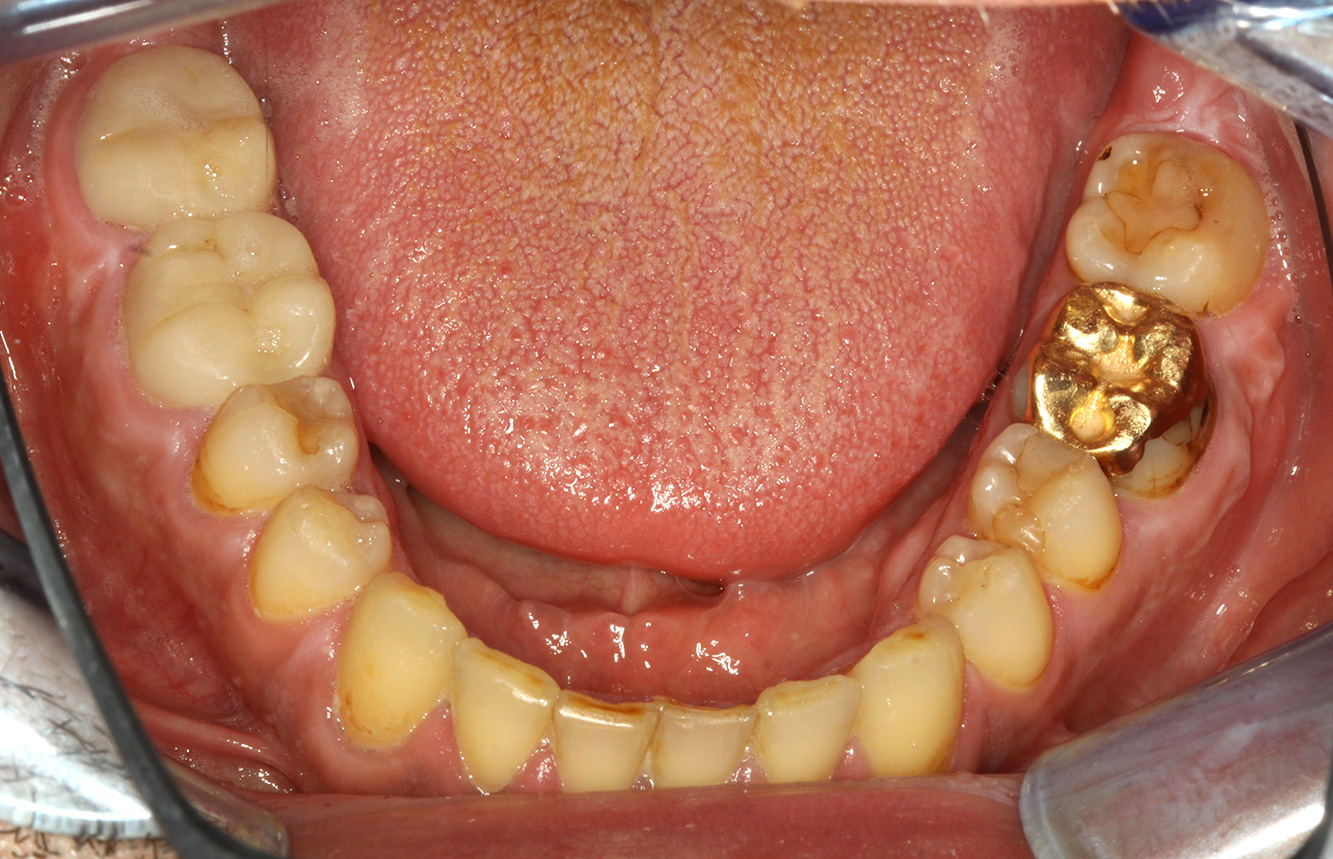

Für die Prophylaxesitzung lassen sich keine spezifischen Instrumentierungsempfehlungen ableiten. Durch den gezielten Einsatz von Pulverstrahl und rotierend Polieren können Plaque und Verfärbungen an den Restaurationsrändern schonend entfernt und Wiederbesiedlungsnischen für kariogene Bakterien reduziert werden (19).

Zur weiteren Unterstützung der Kariesprävention ist eine Fluoridierung, besonders um der Neuentstehung im Bereich der Restaurationsränder vorzubeugen, und eine Versiegelung der Wurzeloberflächen empfehlenswert. Beide Maßnahmen können die angegebene Temperatursensibilität der Zähne reduzieren.